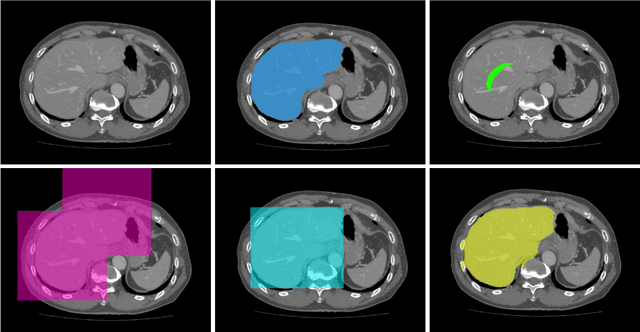

Abstract:To efficiently establish training databases for machine learning methods, collaborative and crowdsourcing platforms have been investigated to collectively tackle the annotation effort. However, when this concept is ported to the medical imaging domain, reading expertise will have a direct impact on the annotation accuracy. In this study, we examine the impact of expertise and the amount of available annotations on the accuracy outcome of a liver segmentation problem in an abdominal computed tomography (CT) image database. In controlled experiments, we study this impact for different types of weak annotations. To address the decrease in accuracy associated with lower expertise, we propose a method for outlier correction making use of a weakly labelled atlas. Using this approach, we demonstrate that weak annotations subject to high error rates can achieve a similarly high accuracy as state-of-the-art multi-atlas segmentation approaches relying on a large amount of expert manual segmentations. Annotations of this nature can realistically be obtained from a non-expert crowd and can potentially enable crowdsourcing of weak annotation tasks for medical image analysis.